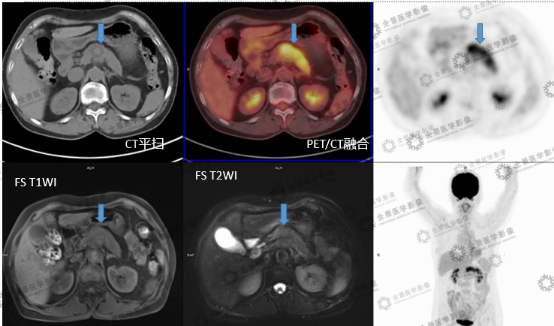

PET\/CT-MR 异机融合

554x326 - 259KB - PNG